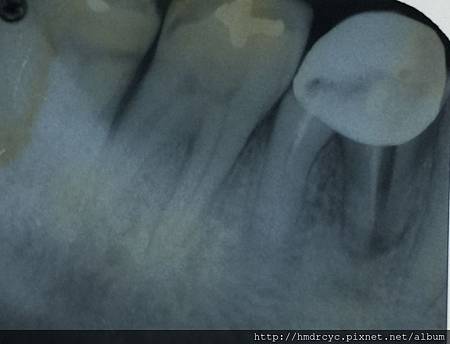

假牙必須利用X光片來更精確的判斷有沒有問題

在X光上面假牙是白色的影像

但X光片判讀困難 所以這部分必須仰賴醫師的專業

1. 蛀牙

蛀牙是常見的問題

X光上則是一個黑色的蛀洞可以參考蛀牙範圍

X光通常會有1-2mm的誤差

所以實際上牙齒裡的洞會比影像大

只要牙套底下出現X光可以辨別的蛀洞

未來繼續蛀牙的速度會很快

牙套內的牙齒也會流失的很嚴重